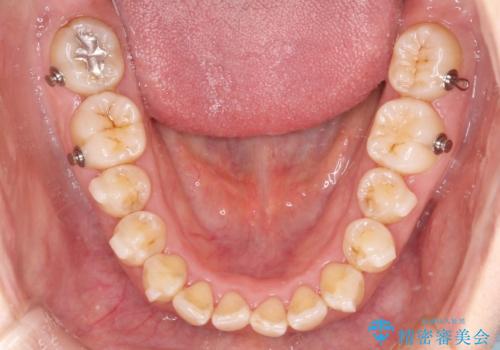

- 矯正装置

- インビザライン

インビザライン は20~22時間の使用が必要となります。